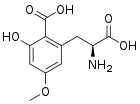

Caramboxin

Caramboxin (CBX) is a toxin found in star fruit (Averrhoa carambola). Individuals with some types of kidney disease are susceptible to adverse neurological effects including intoxication, seizures and even death after eating star fruit or drinking juice made of this fruit. Caramboxin is a new nonpeptide amino acid toxin that stimulate the glutamate receptors in neurons. Caramboxin is an agonist of both NMDA and AMPA glutamatergic ionotropic receptors with potent excitatory, convulsant, and neurodegenerative properties.[84]